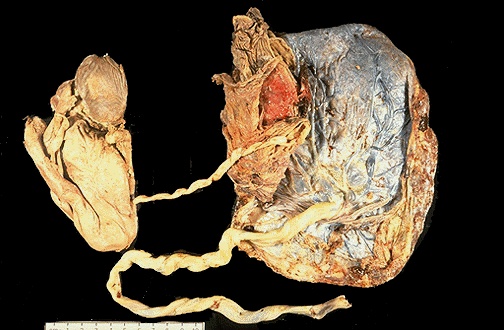

| The markedly macerated fetus at the left was delivered along with the placenta after the liveborn twin was delivered. The reason for the demise here is a "twin-twin transfusion" syndrome in which a vascular anasomosis between the two fetal circulations in a monochorionic twin placenta leads to diminished blood flow to one twin (the "donor") and increased blood flow to the other twin (the "recipient"). The donor may die for lack of blood, or the recipient may die from congestive heart failure. |